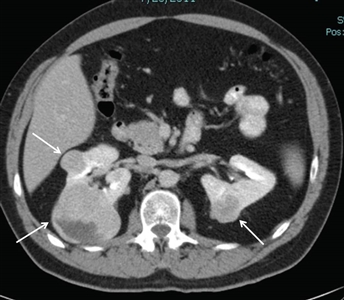

Del 25 % al 35 % de las personas afectadas por el síndrome de BHD presentarán tumores renales,[1,4,10,11] que son multifocales en el 65 % de los casos y, a menudo, bilaterales. La frecuencia de tumores renales en los pacientes con síndrome de BHD fue del 20 % según la revisión de historias clínicas y del 29 % según la evaluación mediante TC. La mayoría de los tumores renales relacionados con el síndrome de BHD son de crecimiento lento. La mediana de edad en el momento del diagnóstico oscila entre 48 y 50 años (intervalo, 31–71 años).[2,12,13,14] Los tumores renales fueron más frecuentes en los hombres que en las mujeres (27 hombres; 11 mujeres). Los tumores renales relacionados con el síndrome de BHD surgen a una edad más temprana que las formas esporádicas del cáncer de células renales (RCC), cuya mediana de edad es de 64 años en el momento del diagnóstico.[15] En la Figura 1 se observan tumores renales bilaterales en un paciente con síndrome de BHD.

Vista de un corte transversal del cuerpo en donde se observan dos tumores en el riñón izquierdo y un tumor en el riñón derecho.

Los tumores más comunes son un híbrido de los tipos histológicos celulares oncocitoma y cromófobo, los llamados tumores híbridos oncocíticos, el carcinoma de células renales cromófobo y el oncocitoma renal. Solo el oncocitoma renal se considera un tumor benigno.[12] Otros subtipos histológicos de tumor renal, como el cáncer renal de células claras (ccRCC) y el carcinoma papilar renal, son poco frecuentes en los pacientes afectados por el síndrome de BHD.[11]